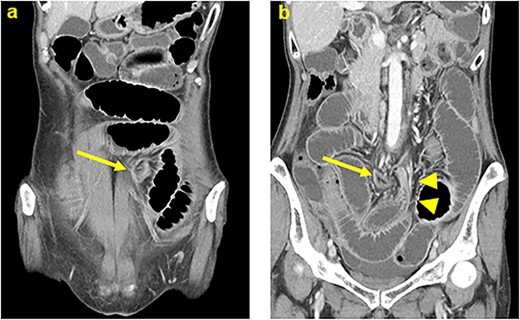

Two months after the surgery, the patent was admitted with moderate tenderness around the umbilicus during a course of adjuvant chemotherapy. Computed tomography revealed dilated small intestine in the lateral space of the lifted sigmoid colostomy with a caliber change adjacent to the left side of the lifted colostomy (Fig. 1). Neither closed loop nor reduced enhancement on the intestine was found. Small bowel obstruction resulting from adhesion or internal hernia associated with the lifted colostomy was suspected. Because her abdominal tenderness disappeared immediately after admission, the patient was managed nonoperatively and quickly recovered. One month later, recurrence of small bowel obstruction occurred, which quickly improved in a similar manner to the last hospitalization. Curative surgery was recommended but not scheduled based on the patient’s wish. However, recurrence of the intestinal obstruction was occurred repeatedly. Finally, curative surgery for repeated small bowel obstruction was scheduled seventeen months after the first occurrence. Laparoscopic surgery was performed using three ports, which were placed on the epigastric, right-upper and right-lower quadrant areas (Fig. 2a). Laparoscopy revealed that the small intestine had passed through a defect between the lifted sigmoid colon and abdominal wall in a cranial-to-caudal direction (Fig. 2b). There were no findings of dilatation and adhesion in the herniated intestine, which was easily restored to the normal position. The hernia orifice between the lifted sigmoid colon and lateral wall was closed by running suture to prevent recurrent herniation (Fig. 2c and d). To prevent loosening of the suture line, barbed suture was used for closing the enlarged hernia orifice. The patient’s postoperative course was uncomplicated, and she was discharged on the fifth day after the second surgery.

Computed tomography showed that dilated small intestine were positioned in the lateral space of the lifted sigmoid colostomy. (a) A caliber change of dilated intestine was found adjacent to the left side of the lifted colostomy (b). Arrows: the lifted sigmoid colostomy; arrowheads: a caliber change of the dilated intestine.